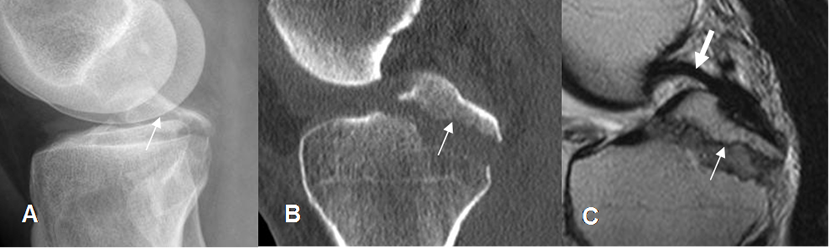

Fig 49. Avulsión de la espina tibial posterior.

A: Rx lateral, B: TAC reconstrucción sagital y C: RM sagital en T2. Avulsión desplazada, de la espina tibial posterior. (Flecha delgada). En la RM se encuentra el LCP íntegro y de aspecto normal. (Flecha gruesa).